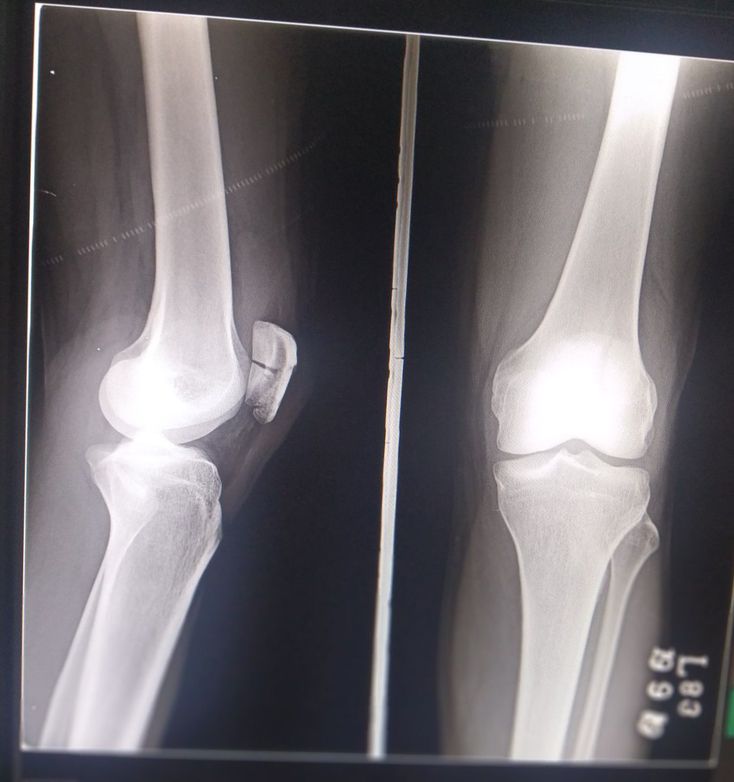

Yes ! It's a patella fracture 😑

Radiology

Xray

Fracture

Radiography

Patella